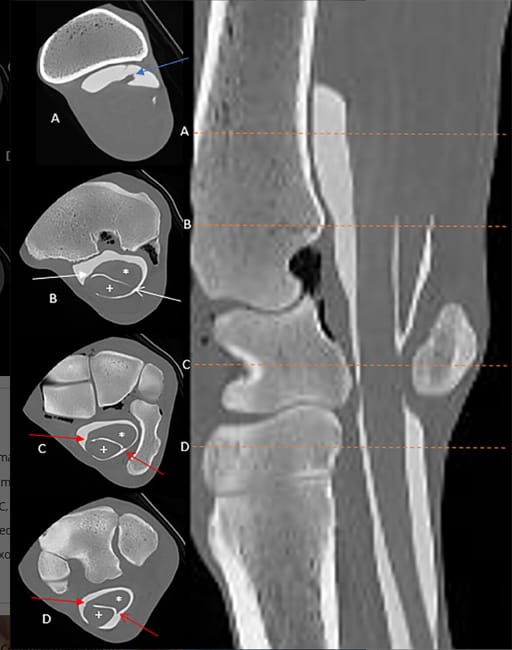

Transverse and sagittal contrast CT images in bone window showing the radial head of the deep digital flexor tendon (A; blue arrow), the proximal mesotenon (B; white arrows, shaded arrowhead is medial) and the manica of the common mesotenon (C, D; red arrows, shaded arrowhead is medial, site of attachment to the common mesotenon). N.B. The dashed orange lines correspond to the transverse sections on the left (images A–D); * is the deep digital flexor tendon, + is the superficial digital flexor tendon.